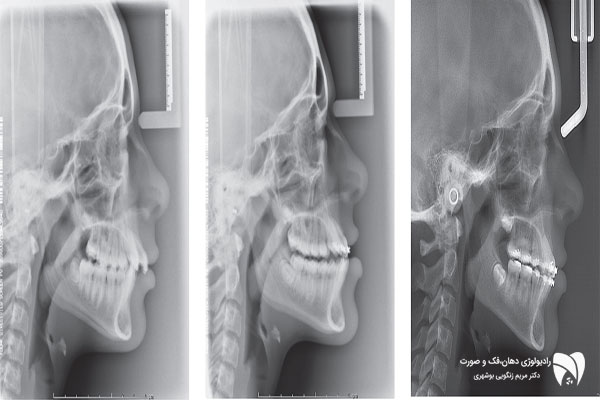

فتوگرافی ارتودنسی شامل عکس هایی از زاویه های مختلف چهره و دندانهاست که باید بسیار دقیق و با کیفیت واز زاویای استاندارد تهیه شود . فتوگرافی ارتودنسی اسکن دقیقی از وضعیت و پارامترهای چهره ، طرح لبخند و دندان های شما به دندانپزشک می دهد و به او کمک می کند تا برای شما بهترین طرح درمان متناسب با پارامترهای صورت طراحی کند و همین طور فرایند پیشرفت درمان را کنترل نماید. با توجه به اهمیت فتوگرافی دندان، بیماران باید در انتخاب بهترین رادیولوژی دهان، فک و صورت دقت بیشتری داشته باشند.

گاهی اوقات در معاینه اولیه دندانپرشک متوجه نقایص و مشکلات بیمار خود نمی شود . فتوگرافی دندان پزشکی و ارتودنسی کمک می کند تا دندانپزشک به دید کلی از وضعیت دندان های شما دست یابد و طرح درمان مناسب ارتودنسی ، ونیرکامپوزیت ، لمینت دندان یا ایمپلنت تجویز کند .عکس پزشکی باید به گونه ای استاندارد انجام شده باشد که پزشک بتواند با استناد به آن طرح درمان دقیقی را طرح ریزی کند .

یکی از مشکلاتی که اغلب دندانپزشک ها با آن دست و پنجه نرم می کنند عدم توجیه بیمار از روند فرایند درمانی خود است . با فتوگرافی می توان مشکل را حل کرد و بیمار را تا حد زیادی از کیفیت درمان خود آگاه کرد .با فتوگرافی می توان نتایج را آنالیز کرد و آن را با وضعیت فعلی بیمار مقایسه کرد تا پزشک و بیمار بتوانند به یک طرح درمان مشترک و قابل پذیرش برسند .